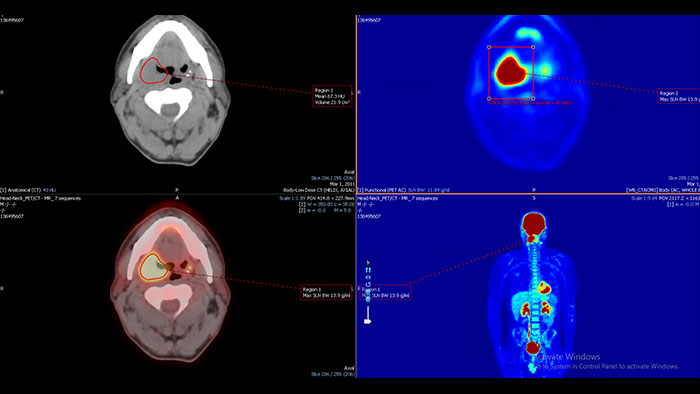

Enhanced user experience for NM reading with a leading NM viewing solution

A comprehensive NM solution, designed to enhance productivity of PET/CT and NM reading. It offers a solution for handling multiple studies requiring rigorous quantification of MV data**.

Assessing Amyloid plaque

The NM NeuroQ Amyloid analysis tool is designed to help clinicians to assess the presence or absence of Amyloid plaque in the brain. Provides quantitative analysis tools for Brain PET scans using NeuraCeq or Amyvid agents.

Benefits